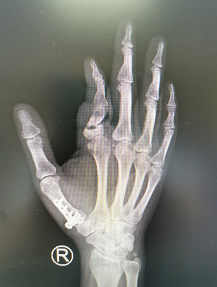

术前

次日,完善了术前各项准备,郑主任、张继朝医生团队为刘先生进行了手术治疗,术中发现近节指骨中段骨质已被肿瘤破坏,首先进行了肿瘤病症的扩大刮除,并对骨面进行抗肿瘤治疗以减少复发几率,然后进行指骨重建,以髂骨植入骨缺损处,纠正畸形并恢复患指长度。手术顺利,术后刘先生手指又恢复了功能及美观。